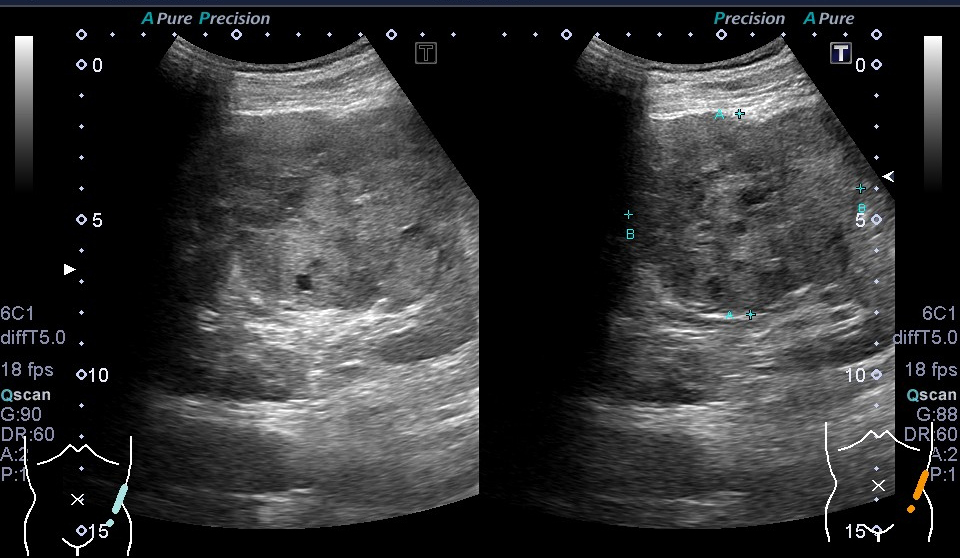

超音波(エコー) 診断画像

- 転移性肝がん

- 腎細胞がん